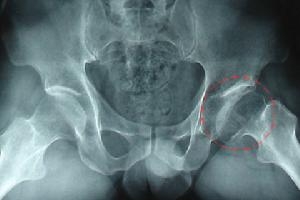

小兒股骨頭壞死病常發於四至八歲之間的男孩子。症狀的出現為漸進性,病童有疼痛、跛行現象,沒有全身症狀,患側髖部活動受制。照骨盤X光時,即可見到股骨頭變形、崩壞、移位現象,而髖臼本身在初期還是好好的,這足以與結核病或其它疾病區別。

Ⅳ期:疼痛劇烈,伴有功能障礙;X線片、CT片上股骨頭變形並有間隙變化或伴有髖關節的變形。

股骨頭壞死的中期症狀:症狀非常明顯,主要有跛行 行走疼痛 功能發生障礙,拍X片時,會看到骨小梁大部分消失,囊狀改變,骨質硬化,股骨頭軟骨斷裂塌陷。

股骨頭壞死的晚期症狀:患者跛行更加嚴重,明顯感到腿短,行走困難,疼痛,X片會看到股骨頭扁平,塌陷,關節間隙狹窄或消失,囊狀改變明顯,骨質硬化面積較大,股骨頭軟骨完全斷裂,關節面粗糙。有的可造成髖關節半脫位,此時的疼痛與髖關節活動、負重有直接關係。活動時關節內因骨性磨擦而疼痛,靜止時頭臼之間不發生磨擦,疼痛也就不明顯了。所以說, 行走、活動疼痛加重,動則即痛,靜則痛止或減輕。